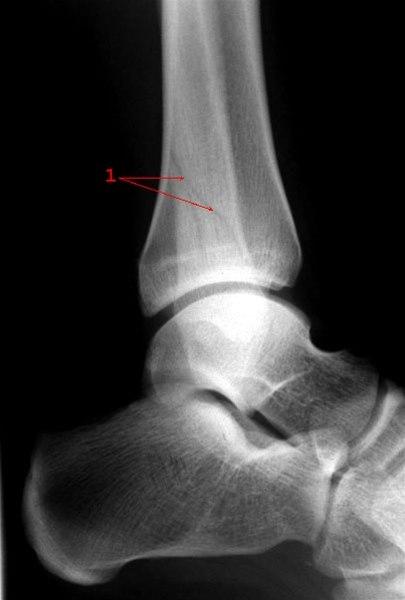

Beinbrudd

Bruddskader kan oppstå i de fleste bein i underkroppen. Sammenstøt, stempling, vridning, lander forkjært kan alle føre til beinbrudd. Langvarig overbelastning kan føre til stressbrudd, trøtthetsbrudd. Bruddskader fører ofte til langvarige skadefravær.

- Ankelbrudd